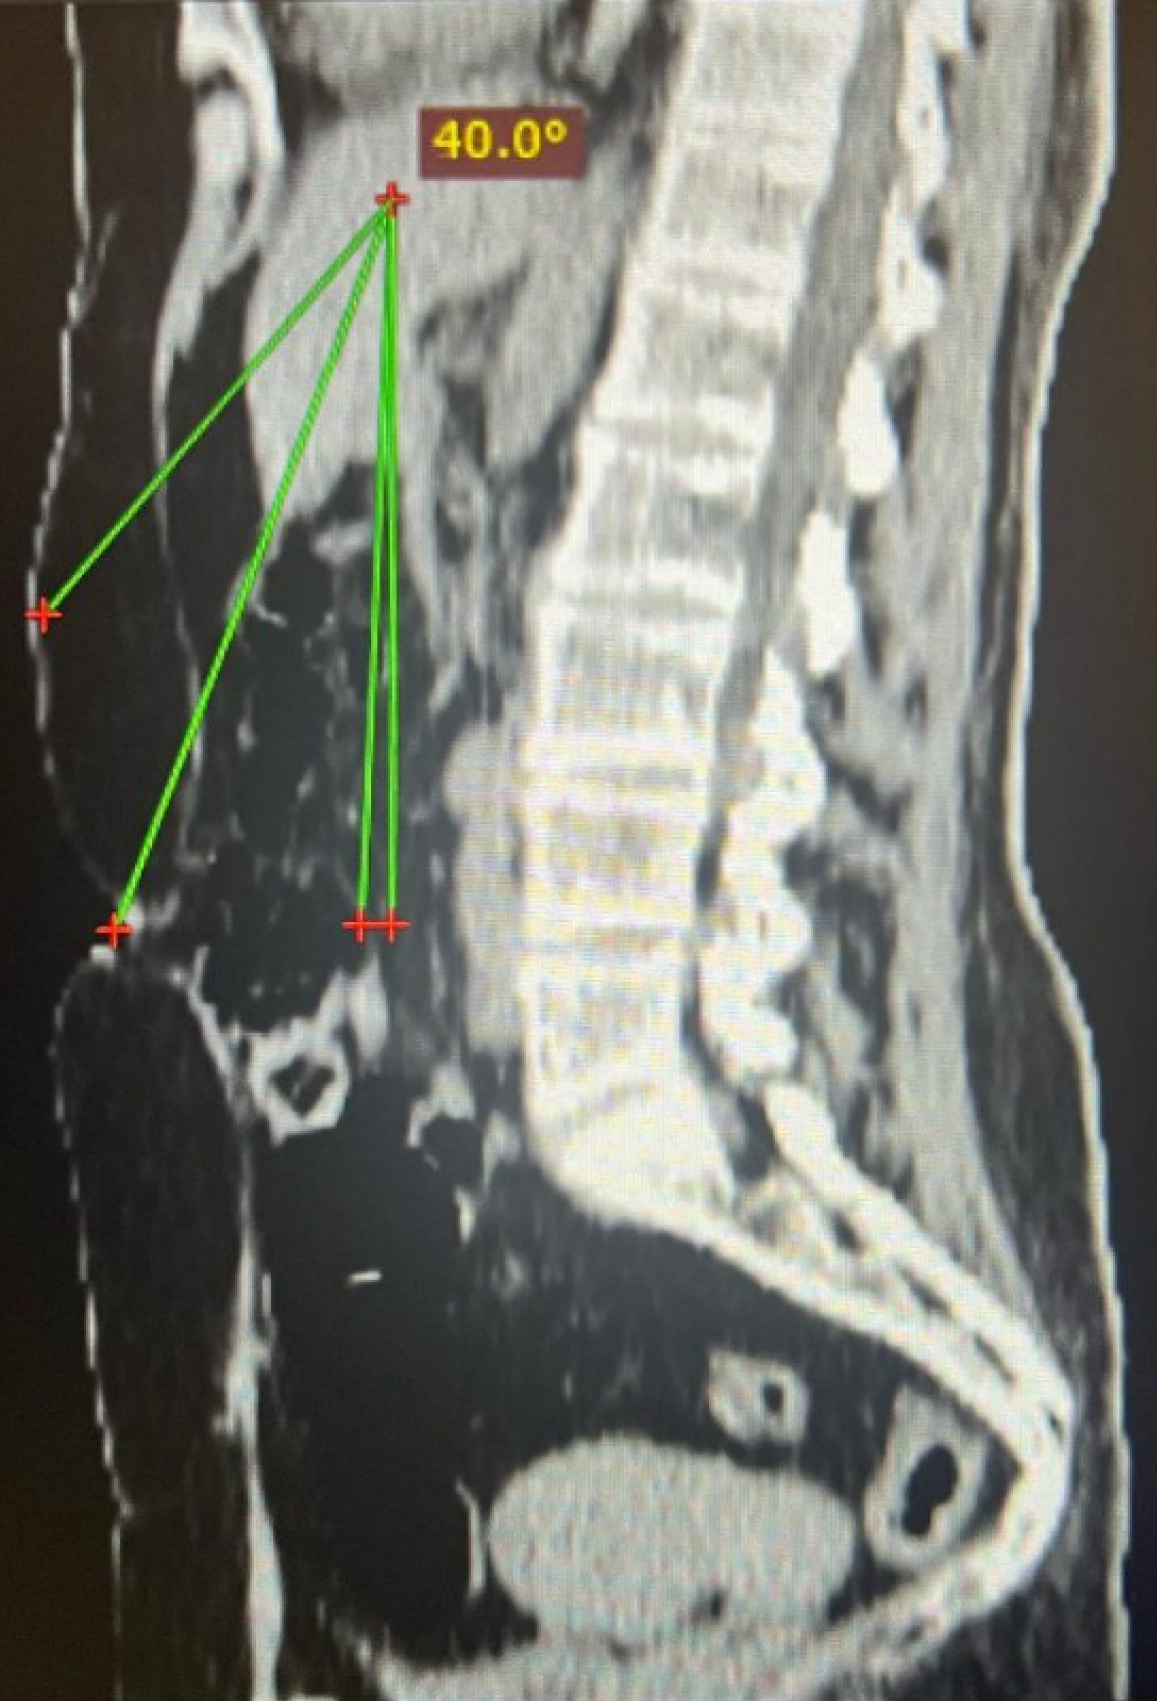

Figure 3 Preoperative organ targeting.